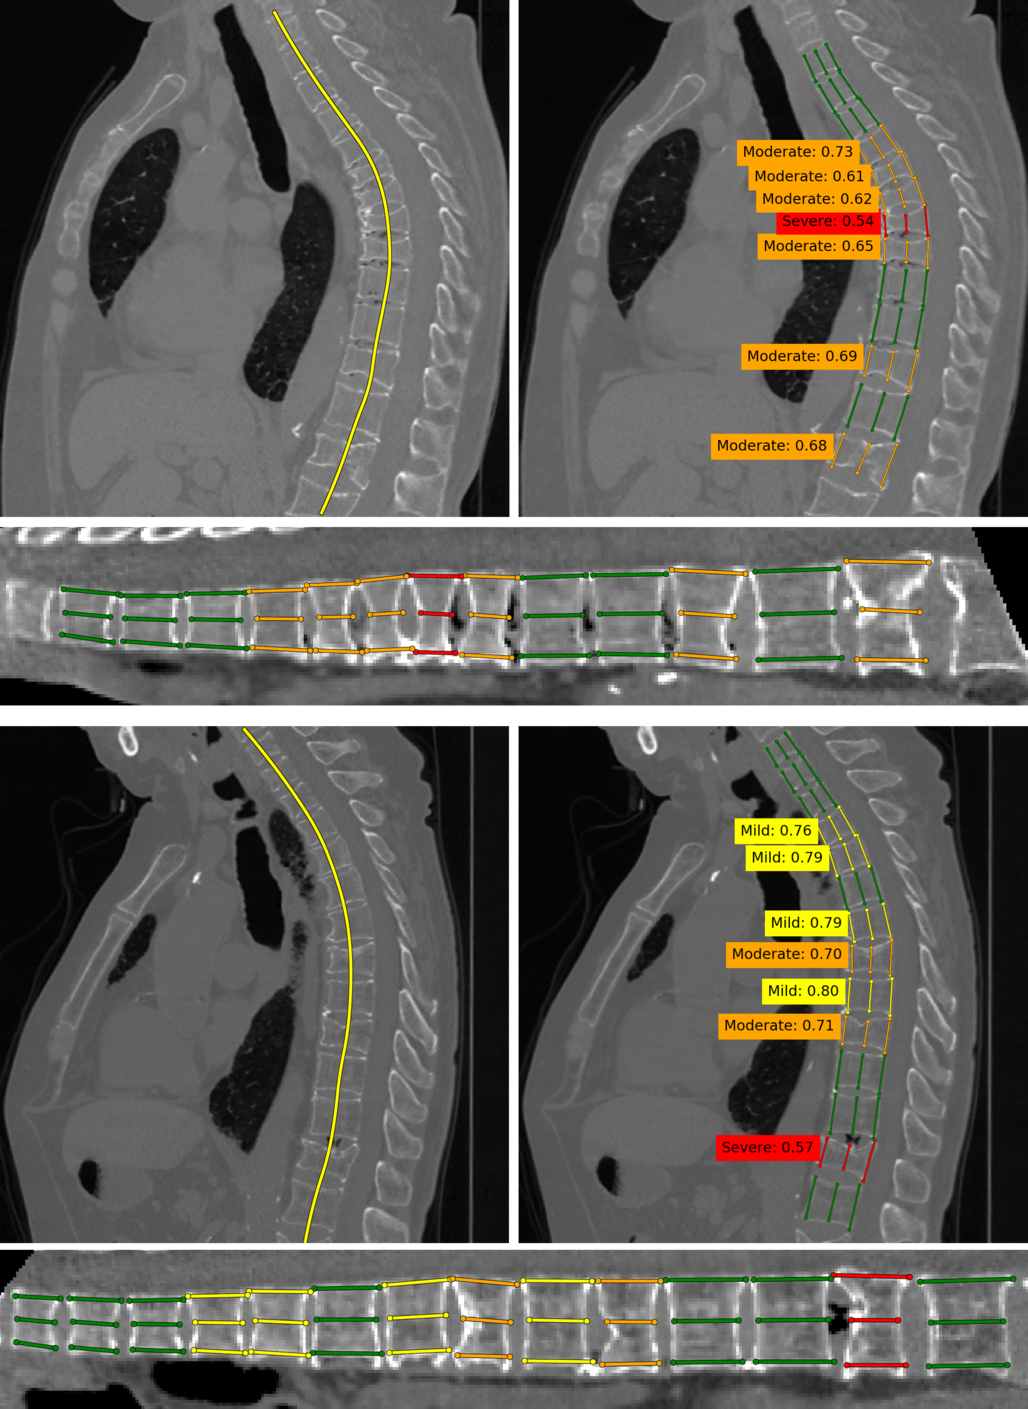

Refer to caption

Figure 4: A simple example from the dataset. Colors denote the fractures severity.